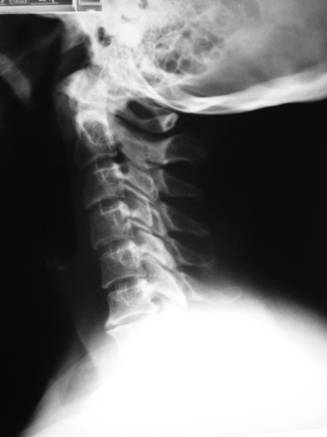

ESTUDIOS DIAGNOSTICOS RADIOLOGICOS Y ELECTRICOS

REFERENCIA DE MARCACION NO CORRESPONDENCIA EXACTA MEMBRANA CRICOTROIDEA : C6 CARTILAGO TIROIDES: C3-C4 ENTRE LOS ANTERIORES: C4-C5 ANGULO DE LA MANDIBULA: C2-C3 DOS DEDOS POR ENCIMA DE CLAVICULA: C6-C7